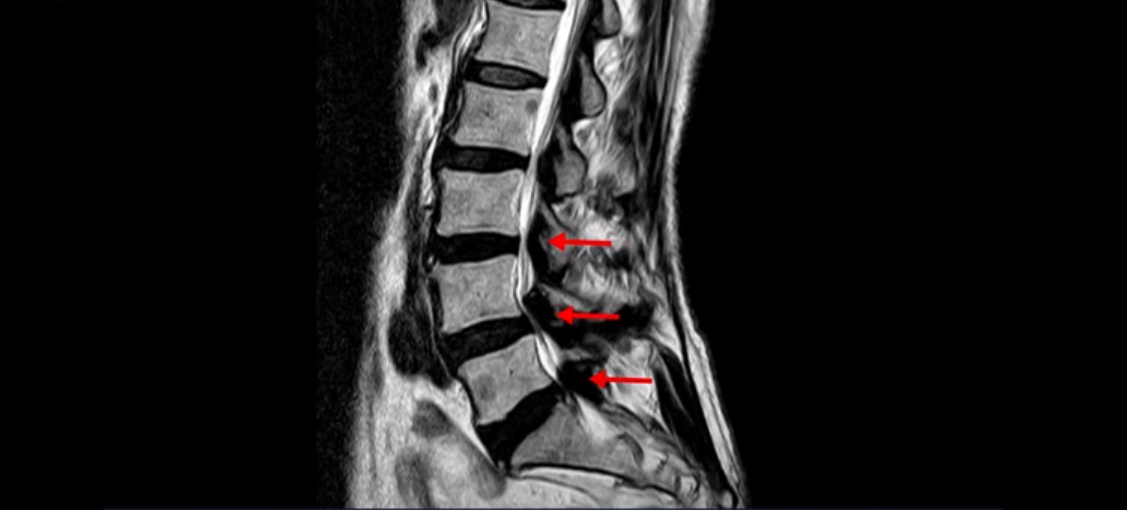

실제 저희 치료후기에 나오는 환자분들의 사례를 들어 설명해드리겠습니다. 이분 MRI를 보면 여러 군데 협착이 있는데,

특히 4번 5번 마디의 중심성 협착이 매우 심한 걸 볼 수 있습니다.

아예 신경이 보이지 않을 정도입니다. 그런데 이분은 이렇게 협착이 심해 보여도 작년 가을까지 아무런 증상이 없었습니다. 협착증의 시작은 가을에 해외여행을 가서 장시간 차량을 타고 이동한 이후 극심한 다리통증과 저림 증상이 발생했습니다. 해외여행으로 허리에 무리가 된 후 허리 근육에 문제가 생기니까 신경 눌림 증상이 시작된 겁니다. MRI로 협착이 심해 신경이 눌려 보이지만 그동안 아무런 증상 없이 잘 살았다는 말은 근육신경재활치료로 근육의 상태를 개선해주면 다시 안 아팠던 상태로 돌아갈 수 있다는 얘기입니다.